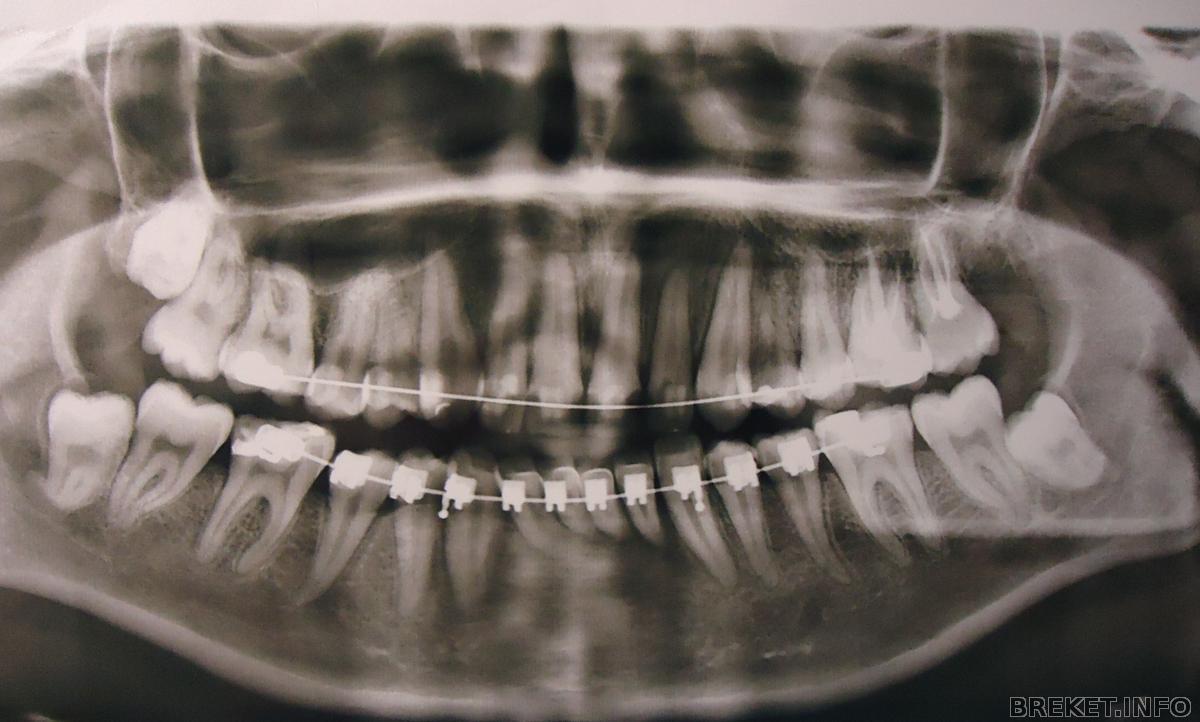

Ребята, удалили мне сегодня вторую по счету 8. Ту которая сверху)

Вырезали с десны, достали. Зашили. Хирург молодой красавчик...ммм..